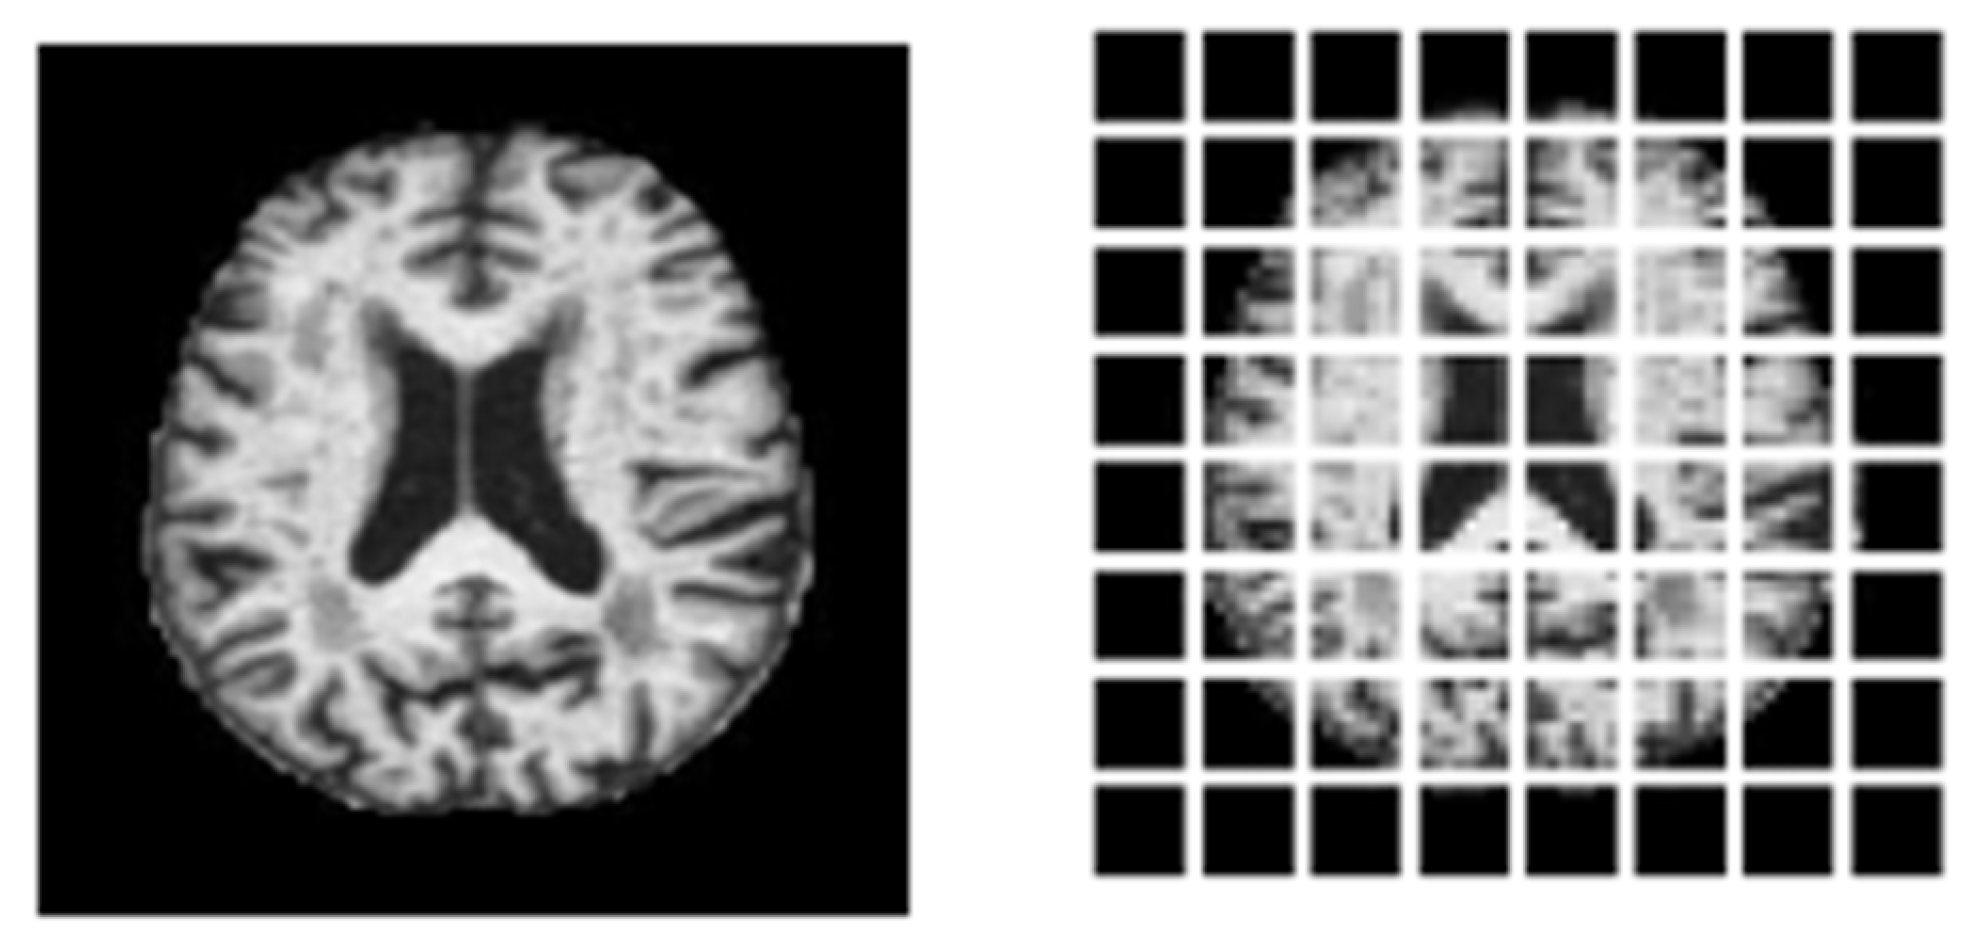

3.1. Dataset Description

3.2. Preprocessing